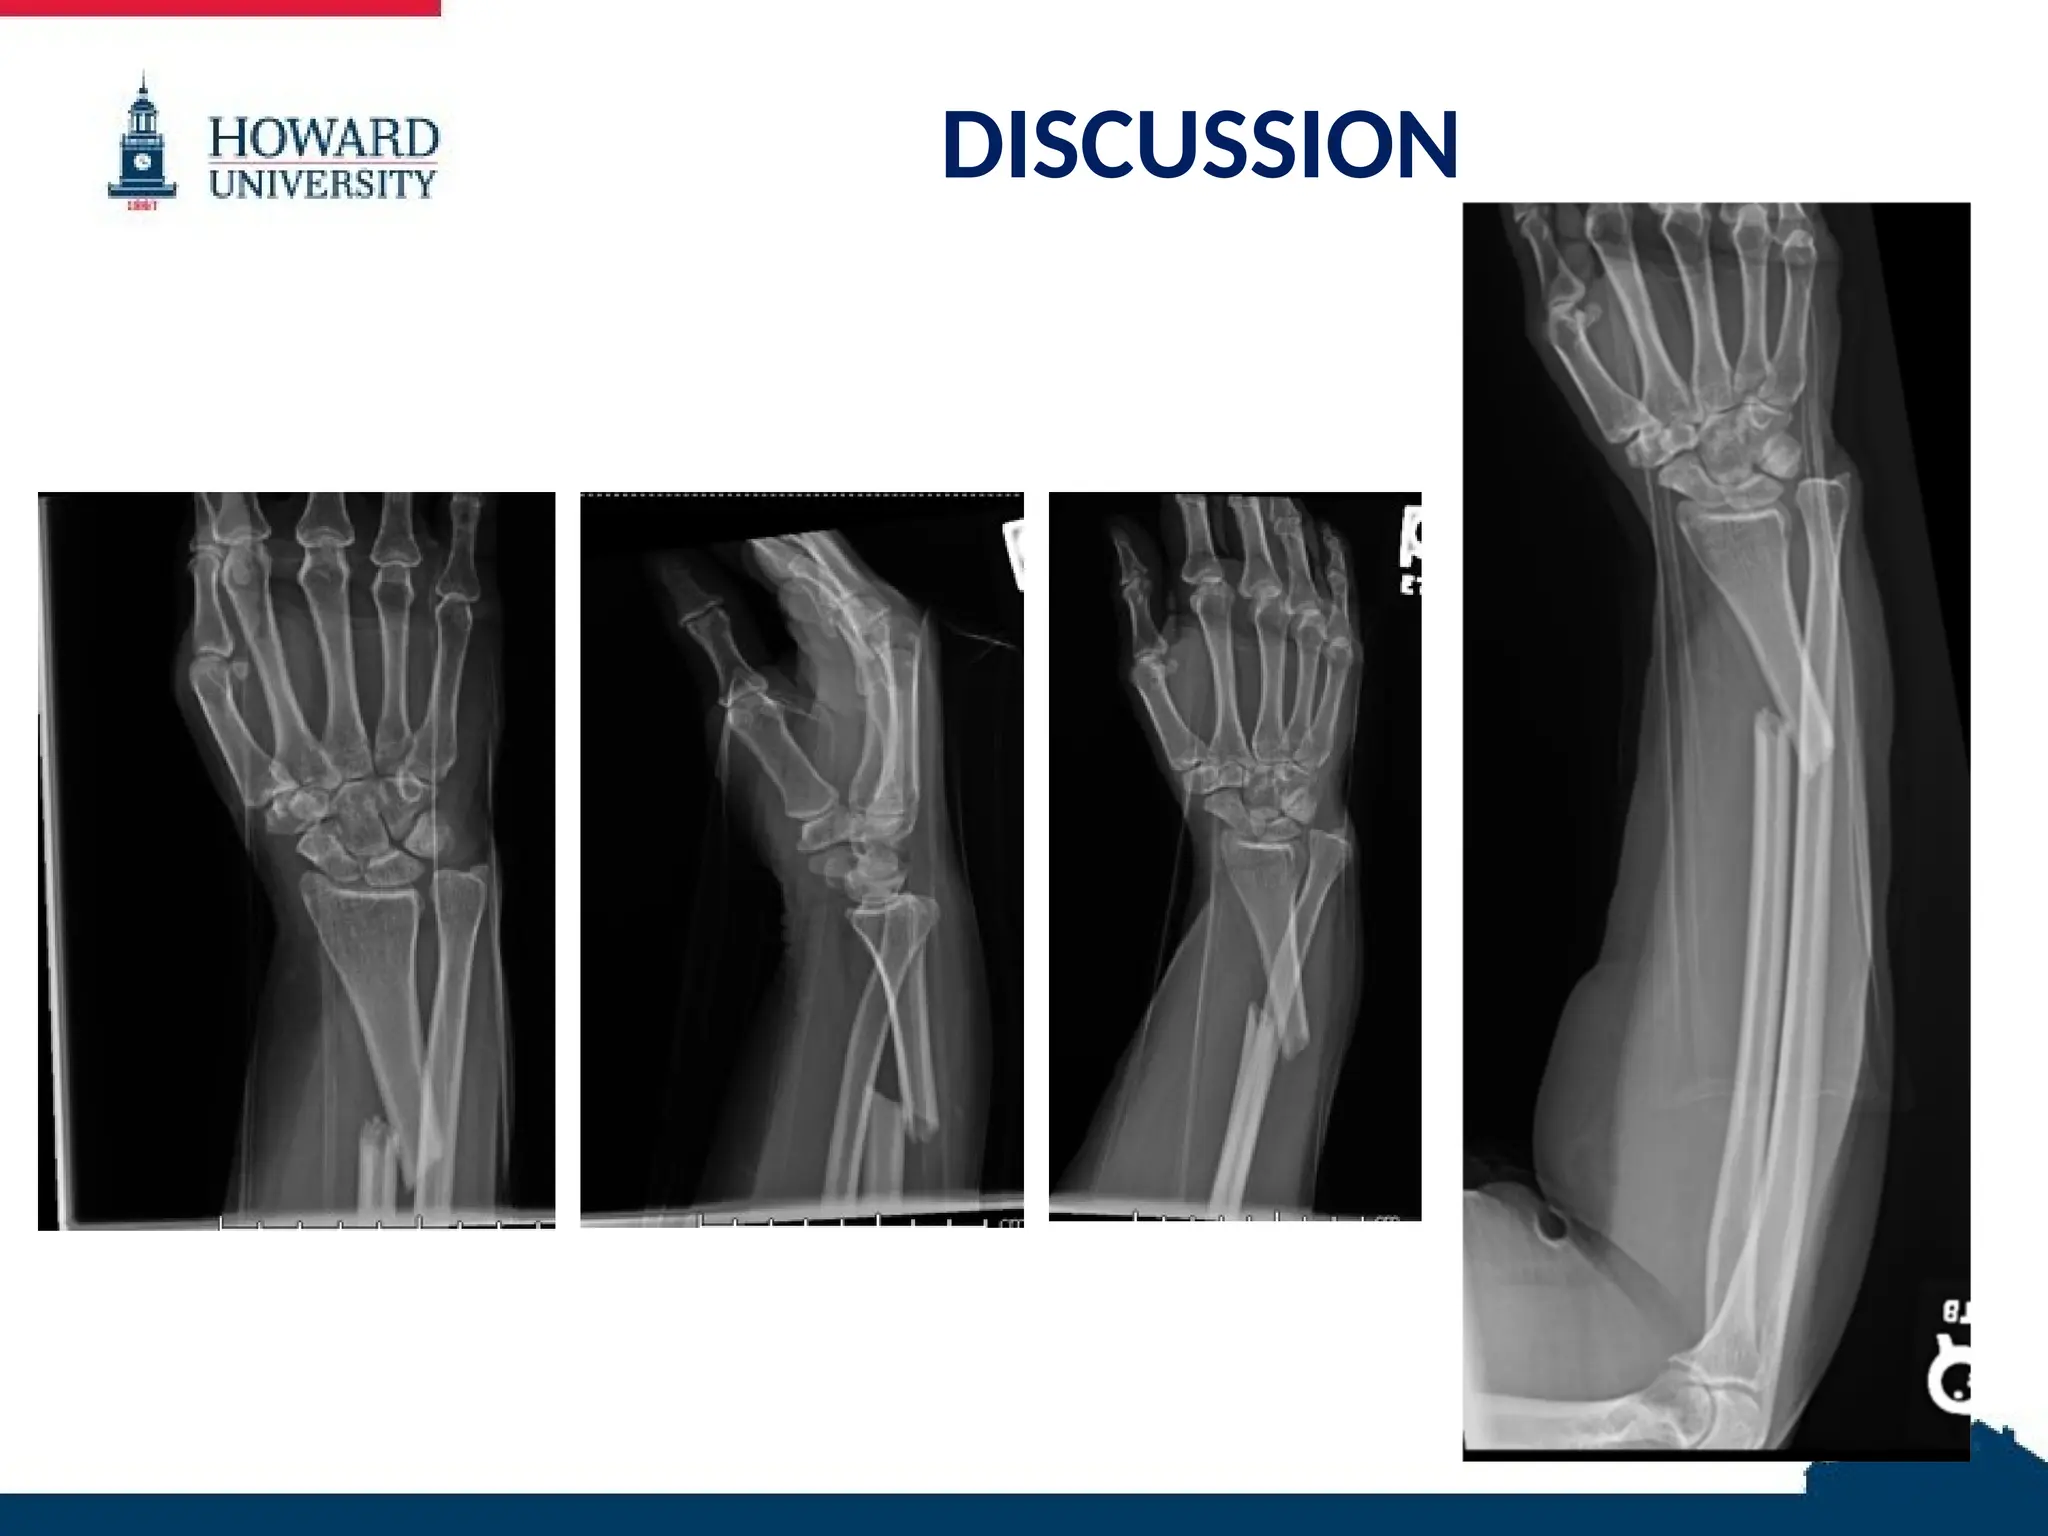

RADIOGRAPHS

59 YO female with right distal 1/3 radial

diaphyseal fracture with associated DRUJ

dislocation

– Walsh type II

– Rettig and Raskin type I

– AO/OTA 22A2.3